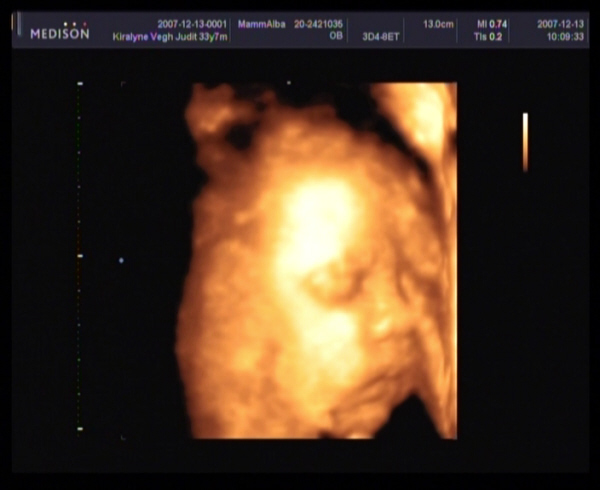

2007.12.13 08:01